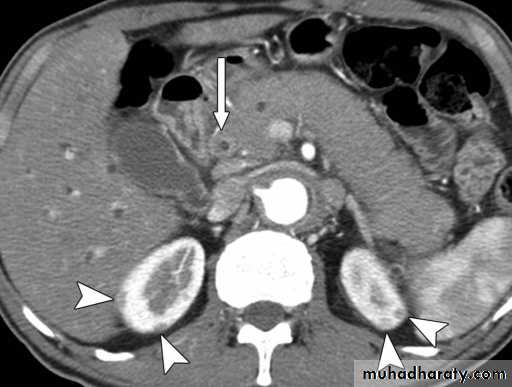

Pancreatitis

Patient present with abdominal pain , vomiting with or without jaundice , increase amylase level

CT finding

Enlargement of the pancreas focal or generalized increase in size .

Hypo density within the pancreas focal or generalized due to the edema .

Peri pancreatic fluid collection & edema around the pancreas .

The fluid around the pancreas if persist more than 6 w become encysted leading to the pancreatic pseudo cyst any area could be affected .

Edema of the wall of the stomach .